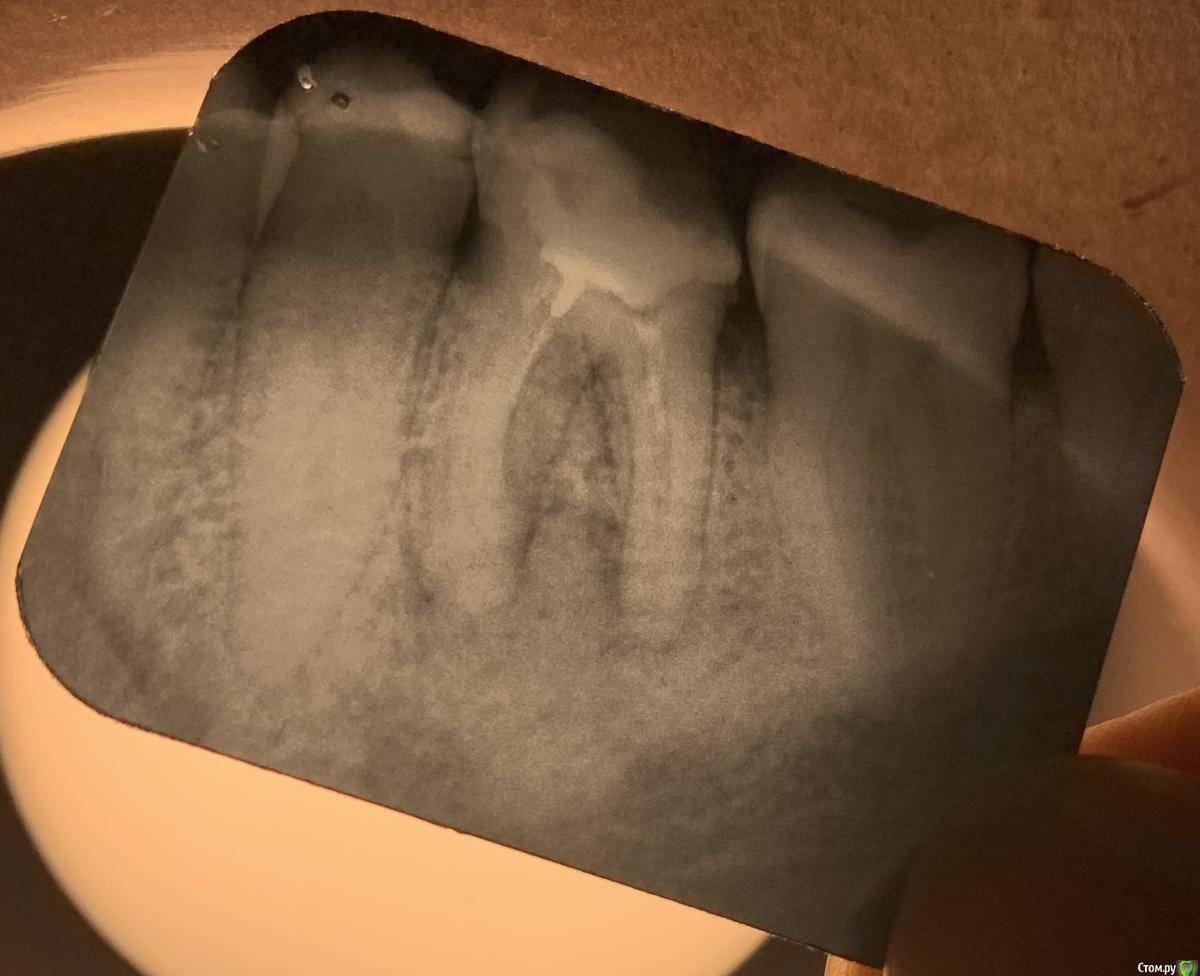

lodo4nik Опубликовано 24 июля, 2020 Автор Поделиться Опубликовано 24 июля, 2020 (изменено) Нашел врача, который согласился повоевать за зуб. Был вчера у него. Каналы пройдены удачно, заложила лекарства, поставила временную пломбу, контрольный снимок через 6 месяцев.Спасибо red_butler за своевременный совет! Изменено 24 июля, 2020 пользователем lodo4nik Ссылка на комментарий

lodo4nik Опубликовано 22 апреля, 2021 Автор Поделиться Опубликовано 22 апреля, 2021 (изменено) 11.08.2020 в 07:43, red_butler сказал: тему можно закрывать, или поделитесь результатом лечения и протезирования? Пожалуй можно и поделиться ? Зуб пролечен и сохранен. Лечение происходило в три посещения. 1. Прошли каналы, заложили временную пломбу на 6 месяцев. Все это время не жевал на эту сторону. Один раз приходил обновить пломбу-стиралась. 2. Пришел к врачу на 1.5 месяца позже установленного (7.5 мес). Что то сделала, поменяла временную пломбу и отправила еще на 1 месяц. Объяснила чем то рыхлым-то ли тканями, то ли каналами. 3. Окончательная пломбировка и восстановление жевательной поверхности. Контрольный рентген через год и через два. Спасибо большое red_butler, за то, что придали уверенности в нужный момент. Изменено 22 апреля, 2021 пользователем lodo4nik 1 Ссылка на комментарий